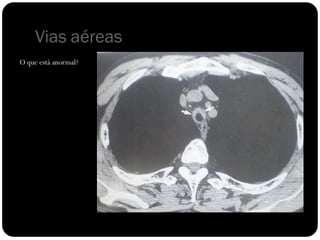

Vias aéreas

O que está anormal?